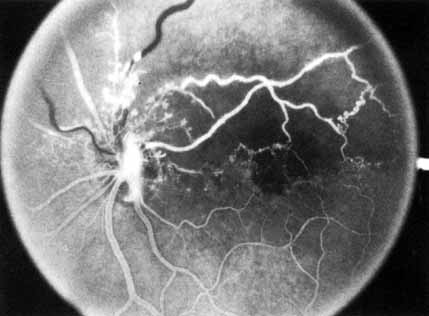

Fig. 3 A and B. Acute nonischemic central retinal vein occlusion in a 36-year-old hypertensive man. His visual acuity was 20/200. C and D. Six weeks later, he presented with eye pain, decreased vision, and neovascular glaucoma. The type of occlusion now is ischemic.

The angiographic pattern may show little except occasionally a prolonged venous transit time. Dilation of the retinal venous circulation, mild staining of the walls of veins, and varying degrees of disc and macular edema may be present (including cystoid macular edema). Capillary nonperfusion is not a prominent feature, nor is its sequela, neovascularization. The electroretinogram is nearly normal, confirming the lack of ischemia.77 The intraocular pressure is frequently lower on the side of the occlusion.78 Synonyms for this type of central retinal vein occlusion have included partial, incomplete, imminent, threatened, incipient, or impending central retinal vein occlusion.60,76 How many central retinal vein occlusions in this category are actually incomplete or partial occlusions that then progress to a more complete occlusion is unknown. It does appear that some eyes with nonischemic central retinal vein occlusion go on to develop a more ischemic type of central retinal vein occlusion (see Fig. 3); whether this represents a progression of the vein occlusion62 or simply progressive retinal capillary nonperfusion is unknown. In series in which the incidence of conversion for the nonischemic occlusion to the ischemic type has been studied, the incidence ranges from approximately 5% to 22%, depending on the duration of follow-up, and is higher for older patients.63,74,79–81

Patients with an ischemic pattern are usually aware of a sudden, painless decrease in visual acuity. Vision ranges from 20/400 to hand movements. The onset, however, is generally not as rapid or the visual loss as extensive as in central retinal artery occlusion. Exceptional cases have been noted in which patients with an acute onset had reasonably good vision and yet demonstrated a picture of ischemic central retinal vein occlusion. Patients with ischemic occlusion have an average age of 68.5 years.66 Confluent hemorrhages are the most prominent ophthalmoscopic feature of an acute ischemic central retinal vein occlusion (see Fig. 3C and 3D). These hemorrhages occur in a wide variety of shapes and sizes; they are usually concentrated in the posterior pole, but may be seen throughout the retina. Hemorrhages in the superficial retina may be so prominent about the posterior pole that the underlying retina is obscured. Many hemorrhages are flame shaped, reflecting the orientation of the nerve fibers. Dot and punctate hemorrhages are interspersed and indicate involvement of the deeper retinal layers. Bleeding may be extensive, erupting through the internal limiting membrane to form a preretinal hemorrhage or extending into the vitreous. Small dot hemorrhages may be seen either isolated or clustered around small venules. The entire venous tree is tortuous, engorged, dilated, and dark. The retina is edematous, particularly in the posterior pole; some of this edema may obscure portions of the retinal vessels. Cotton-wool patches (soft exudates) are often present.

The intravenous fluorescein angiogram pattern of an ischemic central retinal vein occlusion is usually characterized by a delayed filling time of the venous tree of the retina, capillary and venous dilation, and extensive leaking of fluorescein into the retina, particularly in the macular area and in the area adjacent to the larger venous trunks and capillary nonperfusion (see Fig. 3C and 3D; Figs. 4 and 5). Microaneurysms may not be noted at the time of initial occlusion, but are usually manifest shortly thereafter. Late-phase photographs show patchy extravascular areas of fluorescence and staining of the retinal veins. Fluorescence in the macula indicates capillary leakage and edema; this not only may account for much of the initial visual loss in the acute phase, but may also eventually result in permanent structural changes. Intravenous indocyanine green videoangiography may also be helpful in showing the arterial and venous flow alterations in this condition.322